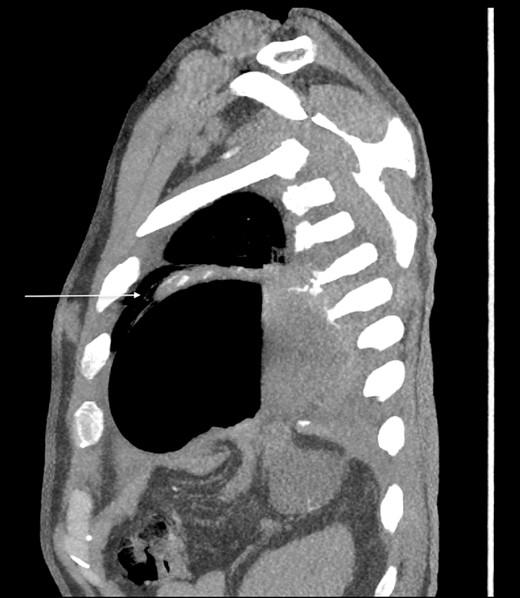

Thirty-seven days after the initial visit, the patient returned to the emergency department with burning epigastric pain that radiated to the left upper chest and hematemesis. Vital signs revealed tachycardia and hypertension. A comprehensive physical exam was significant for decreased breath sounds at the left base and tenderness in the left upper quadrant without signs of peritonitis. Pertinent laboratory findings showed leukocytosis with a left shift and thrombocytosis. A chest X-ray showed a significant portion of the gastric body in the left hemithorax (Fig. 1). A pulmonary CT angiogram found segmental and subsegmental pulmonary emboli in both lungs with no evidence of right heart strain and a left pleural effusion. A left diaphragmatic hernia with the “dangling diaphragm” sign can be seen on the sagittal view (Fig. 2). The coronal view shows discontinuity of the diaphragm and the “collar” sign (Fig. 3); the axial view shows the “dependent viscera” sign and thoracic fluid abutting abdominal viscera (Fig. 4).

Coronal CT showing the gastric body herniating through diaphragmatic defect, discontinuity of the diaphragm (thick arrow), and the “collar” sign (thin arrow).